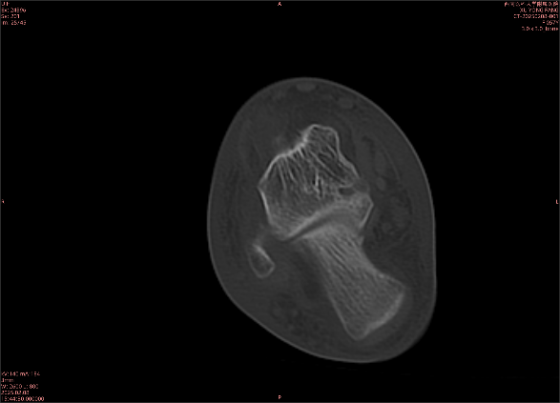

舉例圖像

圖2

專業(yè)解釋看不懂沒關(guān)系,大家看圖1和圖2就可以了,這是同一個(gè)患者跟骨的磁共振和CT圖像,圖1的紅色箭頭指示的黑線就是磁共振圖像顯示的骨折線,一目了然。而對比圖2的CT圖像上并未顯示異常。